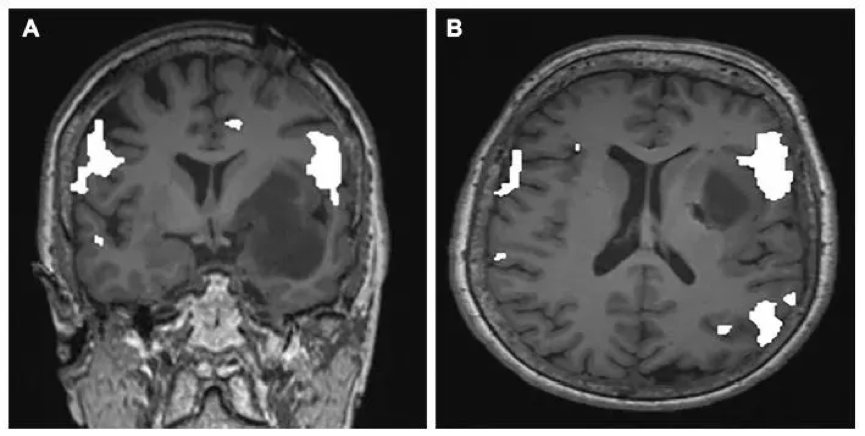

2019年5月,《Neurosurgery》上发表了一则美国神经外科专家等采用分期激光间质热疗LITT新方法,治疗1例位于优势半球岛叶的大型少突胶质细胞瘤(WHOⅡ级)取得满意的疗效的期刊论文,这代表着LITT在更多的疾病方向上扩展着。